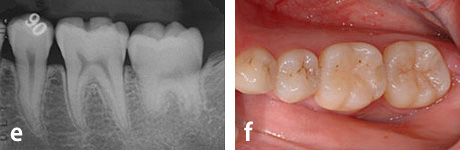

e、f : 移植後6ヶ月

g、h : 移植後3年